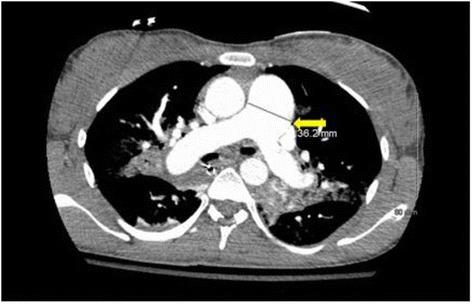

Heterotaxy is a relatively uncommon congenital anomaly that is usually diagnosed incidentally on imaging studies in adults. We present an unusual case of venous thromboembolism in a 26 year old pregnant female with Heterotaxy syndrome.

A 26 year-old pregnant female at 13 weeks gestation suffered cardiac arrest with successful cardiac resuscitation and return of spontaneous circulation. The cardiac arrest was secondary to massive pulmonary embolism requiring thrombolytic therapy and stabilization of hemodynamics. She had extensive evaluation to determine the etiology for the pulmonary embolism and was noted to have an anatomic variation consistent with heterotaxy syndrome on imaging studies. After thrombolysis the patient was treated with UFH and then switched to enoxaparin without complication until 25 weeks of gestation when she experienced worsening abdominal pain with associated headaches, lightheadedness and elevated blood pressures needing elective induction of labor. The infant died shortly after delivery. The anticoagulation was continued for additional 3 months and she was subsequently placed on low dose aspirin to prevent recurrent venous thromboembolic episodes. She is currently stable on low dose aspirin and is into her third year after the venous thromboembolism without any recurrence.